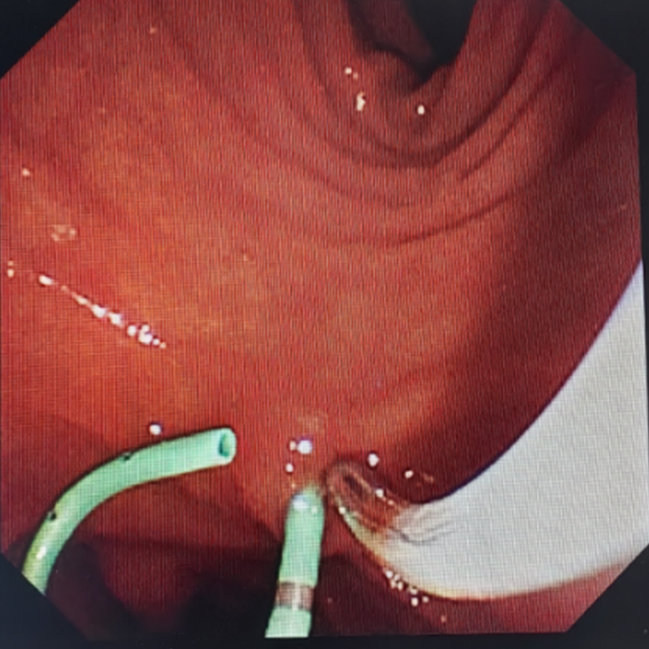

巴桑卓玛副主任医师为6岁的胆总管结石患儿行ERCP下胆道取石术,我院至今已开展儿童ERCP治疗10余例。